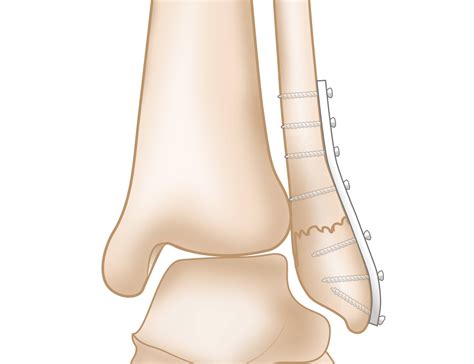

• Open Reduction and Internal Fixation (ORIF): Involves making an incision to realign the bones and using plates, screws, or rods to hold them in place.